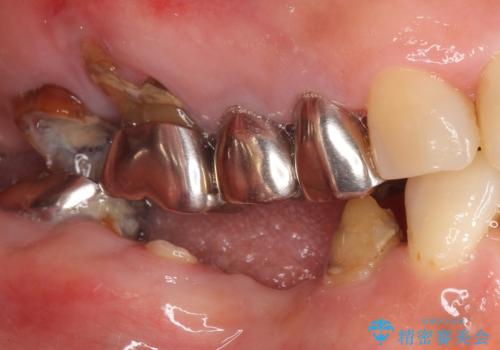

- 奥歯のインプラントをご希望され、来院された患者様です。

骨が薄いため、他院ではインプラントできないと言われたとの事でした。

精査したところ、右下4の根尖病変及び右下5の欠損を認め、右下6は残根となり保存不可能な状態でした。

他にも予後不良な歯があり治療を提案しましたが、ご予算もありご希望されませんでした。

インプラントへの悪影響に関しても説明し、了承頂いた上で治療を行いました。